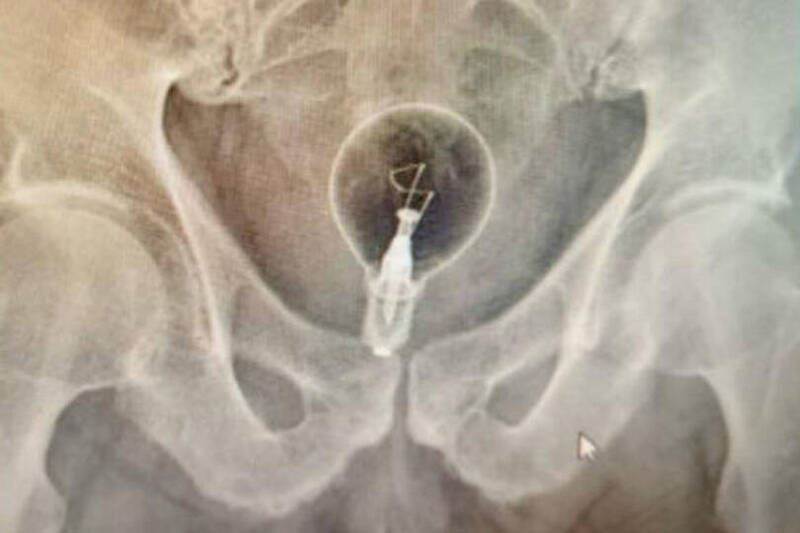

醫護人員到場後立即將老翁送至醫院,經X光檢查確認體內異物為一顆完整燈泡。醫師使用手術鉗將燈泡順利取出,過程中燈泡未破裂,降低了進一步傷害的風險,由於直腸受傷,老翁需住院觀察,所幸並無生命危險。醫師表示,老翁未透露塞入燈泡的原因,但推測可能與「色情實驗」有關。

此類事件雖罕見,但並非首次發生。先前哥倫比亞一名53歲男性因肛門疼痛就醫,經X光檢查發現其直腸內同樣塞有一顆大燈泡,幸運的是燈泡並未破裂,也順利取出。哥倫比亞的腸胃病學家兼內科醫師Julian Pylori提醒,將異物塞入體內不僅容易造成直腸撕裂、出血,還可能導致感染、敗血症等嚴重併發症,呼籲民眾切勿模仿或自行處理。